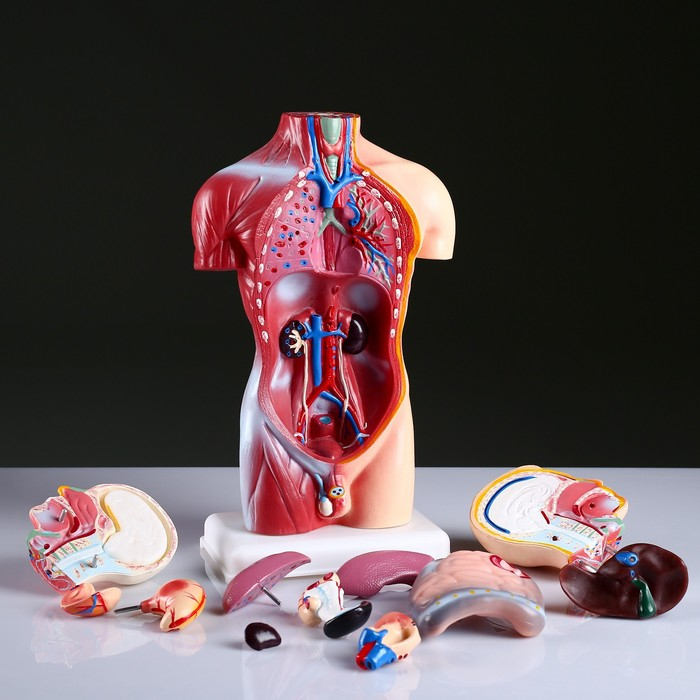

Анатомические модели